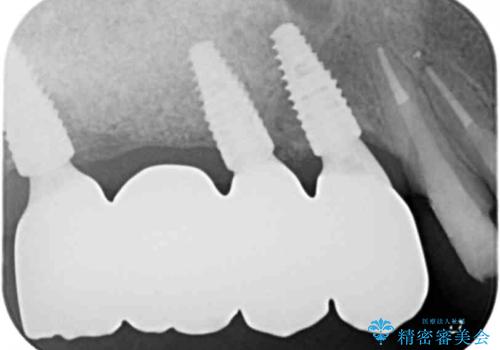

- 275万円(インプラント×5・チタンカスタムアバットメント×5・ジルコニアクラウン×7・仮歯×7)費用は治療当時の料金となります

奥歯を多数失い全く噛めない期間があり、困り果てて来院されましたが、インプラント治療をおこなったことでしっかりと噛めることができるようになりまた食事を楽しめるようになったと大変喜んでいただくことができました。